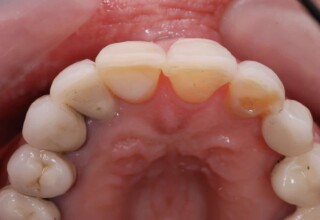

Οι όψεις πορσελάνης είναι ο καλύτερος τρόπος αντιμετώπισης αισθητικών προβλημάτων στην πρόσθια περιοχή του στόματος. Συνδυάζουν συντηρητική αφαίρεση οδοντικής ουσίας και πολύ υψηλή αισθητική απόδοση. Στο παρακάτω εκτεταμένο περιστατικό υπήρχαν: παλαιά σφραγίσματα, δυσχρωμίες, κακό σχήμα και μήκος δοντιών, κακή αναλογία δοντιών-ούλων. Έγινε προσεκτικός εργαστηριακός σχεδιασμός σε εκμαγεία απ’όπου προέκυψαν προσωρινές όψεις που τοποθετήθηκαν στο στόμα για δοκιμή και διορθώσεις. Όταν οριστικοποιήθηκαν οι μετατροπές, οι προσωρινές χρησιμοποιήθηκαν σαν οδηγός για τις μόνιμες. Οι πέντε μόνιμες όψεις πορσελάνης που κατασκευάστηκαν για τα πέντε πρόσθια δόντια της άνω απεκατέστησαν σχεδόν άψογα την αισθητική εμφάνιση της ασθενούς.

Αρχική εμφάνιση

Τελική εμφάνιση